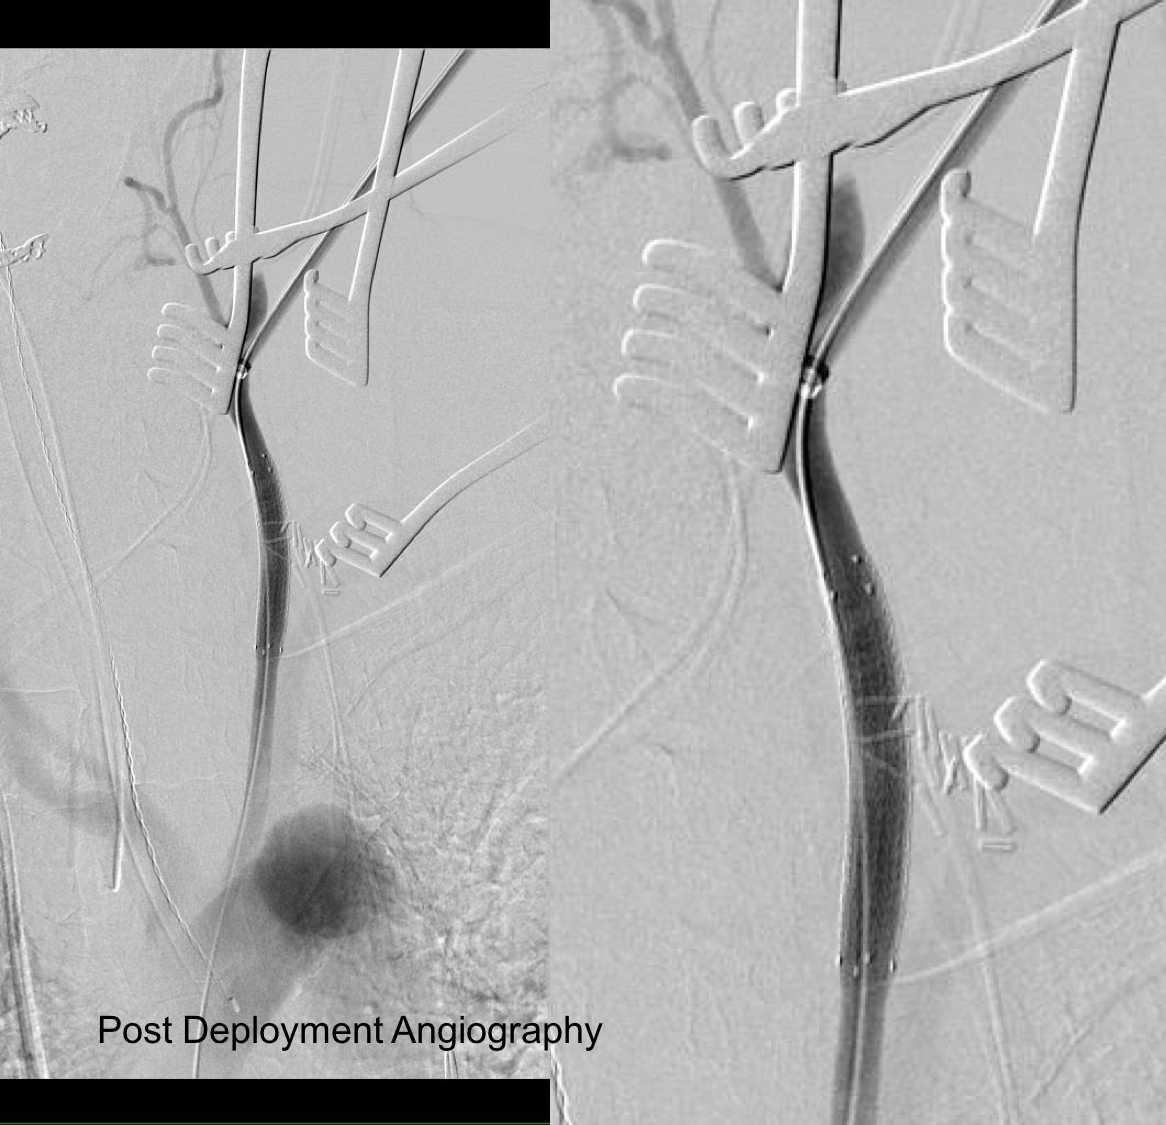

The location of the injury based on CT and on this angio would have baited a younger me into directly exposing it, but experience has taught me that which occasionally you can get away with it, the downsides -massive hemorrhage, stroke, need for sternotomy, just aren’t worth it. The sheath was brought across the injury and a Viabahn stent graft was deployed across the injury.

post deployment angiography.png

The hemorrhage was controlled and the hematoma was then exposed and drained -the cavity was relatively small and accepted the tip of a Yankauer suction easily. A Jackson-Pratt drain was placed. The access site was repaired after flushing and retrograde venting as described.